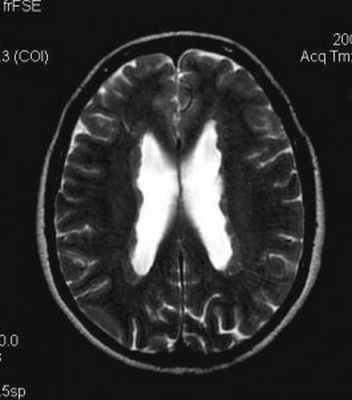

Нейрофиброматоз I типа (болезнь Реклингхаузена) имеет аутосомно – доминантный тип наследования (50%), сцепленный с 17 парой хромосом, или с её спонтанными мутациями. Частота заболевания составляет один на 4000 населения. Диагностическими критериями служат (National Institutes of Health, 1988) не менее 6 кожных пятен (макулы цвета “кофе с молоком” размером не менее 5 мм в пре- и 15 мм в послепубертатном периоде), и не менее 2 любых нейрофибром, либо одна плексиформная (подкожная) нейрофиброма, множественные веснушки в подмышечных и паховых областях, костные дисплазии (истончение кортикального вещества длинных трубчатых костей с коксартрозом или без него, дисплазия клиновидной кости ), двухсторонние глиомы зрительных нервов, 2 или более пигментированные гамартомы радужной оболочки глаза (узлы Лиша) и наличие ближайшего родственника с этим заболеванием. Для постановки диагноза достаточно наличия 2 из перечисленных критериев. Кроме того, характерны следующие сопутствующие патологии: невриномы, кожные нейрофибромы, макроцефалия, астроцитомы, множественные менингиомы, кифосколиоз, саркома Юинга, сирингомиелия. Из опухолей головного мозга наиболее часто (в 5-15% случаев НФ I) встречается пилоцитарная астроцитома зрительного нерва и тракта . На МРТ астроцитома видна в виде утолщения зрительного нерва. Образование изоинтенсивно или немного гипоинтенсивно на Т1-взвешенных МРТ и гиперинтенсивно на Т2-взвешенных МРТ. Среди других локализаций астроцитома может быть в стволе, гипоталамусе, III желудочке. Редко обнаруживаются анапластические астроцитомы полушарий и мозжечка. У детей при НФ I встречаются очаги , напоминающие гамартомы. Они выявляются в ножках мозга, мосте, бледном шаре, среднем мозге, зрительном бугре, продолговатом мозге, реже белом веществе полушарий и мозжечка. На Т2-взвешенных МРТ очаги слегка гиперинтенсивны, на Т1-взвешенных МРТ изоинтенсивны белому веществу, за исключением бледного шара, где они тоже чуть гиперинтенсивны. Они не превышают 15 мм в размерах, не вызывают масс-эффекта и не контрастируются. Предположительно, очаги представляют собой участки изменённого миелина.

Субэпендимальные, то есть проецирующиеся в желудочек, но растущие со стороны паренхимы мозга, узлы чаще расположены рядом с хвостатым ядром или гипоталамической бороздой сразу за отверстием Монро, реже в области III, IV желудочков и Сильвиева водопровода. На Т2-взвешенных томограммах субэпендимальные узлы умеренно гиперинтенсивны и часто содержат кальцинаты . От астроцитом их отличает не столь яркий сигнал и меньшие размеры. Контрастирование при введении препаратов гадолиния иногда наблюдается и в субэпендимальных узлах , и всегда в астроцитомах.

Туберозный склероз. Субэпендимальные узлы. Аксиальная Т-зависимая МРТ.